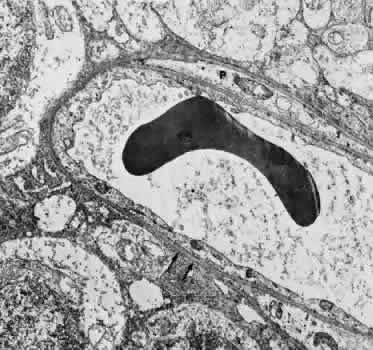

Retinal Veins and Venules Retinal veins are present in the inner retina, where they occasionally interdigitate with their associated arteries. When the two vessels cross, the artery usually lies anterior (toward the vitreous) to the vein.16 About one third of the time, however, the vein is anterior. At such crossing sites, the two vessels share a common adventitial coat.17 Under normal circumstances, the crossing vein's lumen may be decreased by as much as one third as a result of compression from the accompanying artery.17 There are many more arteriovenous crossings temporally than nasally, because the nasal vessels assume a much straighter course. Arteriovenous crossings are important because they represent the most common site of branch retinal vein obstructions. The separation of the superior and inferior halves of the perfusion of the retina is mirrored in the venous drainage pattern as well. Rarely does a retinal vein cross the horizontal raphe under normal circumstances. The retinal veins drain into the CRV, which also acts as the major efferent channel for the vessels of the optic nerve. Near the disc, the retinal veins are approximately 150 μm in diameter. Throughout the retina, the veins and venules generally follow the course of the arteries and arterioles. The intima of the veins consists of a layer of endothelial cells surrounded by a basement membrane continuous with that of the innermost layer of smooth muscle cells of the media. The media of the largest veins in the posterior retina consists of several layers of longitudinally oriented smooth muscle cells. The adventitia makes up the greatest part of the vessel wall and consists of loosely arranged collagen fibers and adventitial cells and is in direct contact with the glial cells of the retina. Venules are usually less than 20 μm in diameter.15 The media is composed of a single layer of cells resembling pericytes, containing poorly developed myofilaments and dense bodies. Elastin is not present. The adventitia contains little other than the basement membrane surrounding the pericyte (Fig. 5). Retinal Capillaries Throughout most of the posterior retina, the retinal capillaries are arranged anatomically in a dual layer. The superficial capillary layer is associated with the ganglion cell layer, whereas the deep capillary layer resides within the inner nuclear layer. Like capillary networks elsewhere in the body, the retinal capillaries assume a meshwork configuration to ensure adequate perfusion to all retinal cells. The deeper layer has a mesh diameter (i.e., the distance betweencapillaries) that characteristically averages 50 μm in diameter but varies between 15 and 130 μm. The more superficial layer has a slightly larger meshwork, on average 65 μm in diameter (16 to 150 μm). In the midequatorial and anterior zones, where the retina is thinner, only one capillary layer is present. In the fovea and the far retinal periphery, retinal capillaries are absent. The precise anatomical localization of the superficial layer of retinal capillaries appears to depend on the thickness of the accompanying ganglion cell layer.18 In the foveola itself and in the immediate parafoveal retina that contains a ganglion cell layer less than 15 μm thick, there are no superficial capillaries. This area represents the foveal avascular zone. Pathologic conditions that feature retinal capillary dropout, such as diabetes mellitus and sickle cell disease, may show an enlargement of this foveal avascular zone. Near the foveal margin, where the ganglion cell layer is of moderate thickness, the superficial retinal capillaries can be found in the outer aspect of the ganglion cell layer. In the intermediate parafoveal area, which has a ganglion cell region thicker than 45 μm, the superficial retinal capillaries are present within the ganglion cell layer itself. In the perifoveal region, where the ganglion cell layer is two to four cells thick, the superficial capillaries are found along the inner boundary of the ganglion cell layer, in contact with the nerve fiber layer. The major retinal vessels, especially the larger ones, usually are in contact with both the inner and outer boundaries of the ganglion cell layer. A capillary-free zone is present around each of the larger retinal arteries and veins (Fig. 6). It is more prominent around the arteries, measuring up to 100 μm. The capillary-free zone is a product of the embryologic vascular remodeling process. Direct diffusion of oxygen through the walls of the large retinal vessels probably initiates this process of vascular remodeling. Embryologically, numerous capillary-sized channels retract from the developing artery, leaving only a relatively few right-angled side-arm channels to serve as precapillary arterioles. In keeping these side channels to a minimum, the maintenance of an adequate pressure head for the remainder of the retina is ensured. In contrast, the radial peripapillary capillaries (RPCs) may develop in a different fashion, later than the other capillary beds, after vascular remodeling has already occurred.19 A distinct layer of capillaries, the RPC, is found adjacent to the optic disc, most prominently in the superior and inferior temporal aspects of the posterior pole (Fig. 7).20 These capillaries originate only from intraretinal arterioles and not from the optic disc vasculature. They are found within the inner aspect of the nerve fiber layer, making them the most superficial of all retinal capillaries. The RPCs tend to follow relatively long, straight paths, having few anastomoses with adjacent or underlying capillary beds. The RPCs do not traverse the central macular area. Their distribution suggests some anatomical correlation with various diseases. Cotton-wool spots are found in a distribution similar to the RPCs, and the arcuate scotoma seen in glaucoma appears to correspond to their pattern as well.21 The superficial peripapillary hemorrhages seen in glaucoma (Drance hemorrhages) may originate with the RPCs as well.22 Retinal capillaries range in diameter from 4 to6 μm. The capillaries throughout the retina, including those of the radial peripapillary network, have the same fine structure.23 The capillary wall consists of a continuous layer of flattened and longitudinally oriented endothelial cells and an incomplete layer of longitudinally oriented pericytes (Fig. 8). The pericytes (formerly referred to as mural cells) are closely spaced, resulting in an approximate ratio of pericytes to endothelial cells of 1:1, a relatively high ratio compared with elsewhere in the central nervous system. Ultrastructural examination of the endothelial cells of retinal capillaries shows that the cytoplasm of the cell bulges in the region of the nucleus. This area contains the Golgi apparatus, centrioles, and rough-surfaced endoplasmic reticulum. The remainder of the cytoplasm contains moderate amounts of smooth endoplasmic reticulum and mitochondria. The average endothelial cell thickness is 236 nm. Pinocytotic vesicles occur in the cells of the retinal capillaries. The vesicles are of uniform size, with an average diameter of 70 nm. Pinocytotic vesicles are found on the lumen (10% of total) and basement membrane (28%) side of the endothelial cells and free in the cytoplasm (62%). Approximately 2% of the volume of the endothelial cell is occupied by pinocytotic vesicles, a number that is substantially lower than that of other continuous capillaries. Pinocytotic vesicles of similar morphology and location are found in pericytes, but not in any number on glial cell membranes. Animal experimental evidence shows that these vesicles may be responsible for transporting substances from the vitreous cavity into the retinal vasculature in a unidirectional fashion.24 In the region of the endothelial cell junctions, cytoplasmic processes may overlap and form flap-like extensions that project into the lumen. The outer leaflets of adjacent endothelial membranes form very tight occluding junctions. The basement membrane surrounding the endothelial cell is well developed and continuous with the basement membrane surrounding the pericytes. The basement membrane of the retinal capillaries is structurally similar to that of the retinal arteries and veins in that collagen types 4 and 5, laminin, and heparin sulfate proteoglycan core protein are prominent features. Collagen types 1 and 2 appear to be lacking.12 Some areas show thinning of the basement membrane, and in these regions the endothelial cells and pericytes are closely apposed. Specifically, the capillary basement membrane between pericytes and endothelial cells is much thinner than the basement membrane covering the two types of cells.25 This arrangement probably allows increased communications between the cells. The retinal capillary basement membrane is thicker than in most other capillaries in the body, and in certain disease states such as diabetes, this thickness increases further.26 The pericytes of the retinal capillaries are not as elongated as the endothelial cells. They are endowed with multiple arm-like processes that wrap around the surrounding endothelial cells. Pericyte processes appear to cover about 85% of the entire circumference of the available capillary endothelial tube.25 Pinocytotic vesicles can be seen near the adventitial (outer) side of the cell body. In the peripheral retina, the retinal glial cells are in direct contact with the basement membrane surrounding the pericytes. Evidence suggests that the retinal pericytes are directly involved in the local control of retinal blood flow (RBF) and may affect endothelial proliferation as well.25 In diabetes there is an early, preferential loss of pericytes.27 Aldose reductase has been shown in the human pericyte, inviting speculation that abnormal accumulation of byproducts of this enzyme, such as polyol, may have a role in the selective pericyte loss.28 With aging there occurs a gradual loss of endothelial cells, followed by degeneration of the pericytes, an increase in capillary diameter, and a thickening and vacuolization of the capillary basement membrane surrounding the external surface of the pericyte.26,29 Age-related studies of larger retinal vessels show narrowing of the retinal arteries. This appears to be due to the fibrous replacement of contractile elements.17,30 These morphologic findings may account for the decrease in reactivity of the retinal arteries and arterioles to blood pressure and oxygen tension changes with age. A similar decrease in myogenic tone of the PCAs with age has also been demonstrated.31 OPTIC NERVE Most of the blood supply to the intraorbital portion of the optic nerve is through numerous perforating vessels from the pia mater. These pial vessels obtain their supply either directly from the ophthalmic artery or indirectly from recurrent branches back from the PCAs. There does not appear to be a “central artery of the optic nerve,” as once postulated.32,33 Axial branches off the CRA contribute to the circulation as well. The vascular supply of the optic nerve head was the source of considerable controversy in the past. The optic nerve head is situated at the watershed area between three separate circulations: the retinal, the posterior ciliary, and the pial (Fig. 9). Each of these systems contributes in part to the optic nerve head circulation. In some people, an incomplete arterial ring is formed within the sclera by the anastomoses of these three circulations. When present, it is referred to as the circle of Zinn-Haller. Most of the prelaminar blood flow is derived from the posterior ciliary circulation by way of the short PCAs.34,35 The prelaminar optic nerve may have separate tributaries from the short PCAs, or branches of these vessels may supply the optic nerve directly, as well as the choroid.36 There do not appear to be any direct anastomoses between the choriocapillaris and the capillaries of the optic nerve head, however. Neither are there major contributions from axial branches of the CRA. The circle of Zinn-Haller may contribute to the prelaminar circulation, but the pial arteries do not directly supply the prelaminar portion. They may anastomose with the prelaminar capillary network, however. The laminar portion of the optic nerve head is also supplied by the short PCAs, with variable contributions from the circle of Zinn-Haller.37 The CRA does not appear to contribute much to the supply of this area (Figs. 9 and 10).

In the retrolaminar zone, the contribution of the choroidal vessels is less. The peripheral aspects of the postlaminar optic nerve are supplied by the pial vessels, whereas the central portion is fed by the axial vessels off the CRA. The afferent channels derived from the short PCAs that cross the border tissue of Elschnig at the level of the choroid have a diameter ranging from 10 to 17 μm.36,37 They quickly branch into a tridimensional vascular network with a polygonal capillary bed. The capillary bed is nonfenestrated, with tight junctions. Numerous pericytes surround the endothelial cells. The capillary mesh measures from30 × 50 μm to 50 × 80 μm, and there are multiple arterial feeding points into the meshwork. The density of the meshwork seems equal in all disc quadrants. Although the capillary bed of the optic nerve head is derived mostly from posterior ciliary vessels, it more closely resembles the retinal capillary bed morphologically than the choriocapillaris. The major efferent vessel for this area of the optic nerve is the CRV. Some of the prelaminar drainage may be through the choroid as well. Direct communications between the CRV and choroidal veins may exist as a result of CRV obstruction or as anatomical variants, which would make the eventual drainage system the vortex veins. The surface capillaries of the optic disc are derived from the retinal vessels.35,37 They anastomose with capillaries of the retina. The prelaminar, choroidal-derived vessels may contribute somewhat to the surface capillary supply. The postcapillary venules that drain the RPC system cross over the disc margin to join with larger venules of the CRV system. It may be these terminal endings of the RPC that bleed with papilledema and other causes of disc swelling. The blood flow to the optic nerve head appears to be under local autoregulatory control.38–40 This flow pattern is similar to the retinal circulation. The site of the autoregulation is not clear; however, both endothelial cells and pericytes probably have a role. The clinical appearance of optic nerve blood vessels in various pathologic conditions has been the focus of intense interest. Alterations in optic nerve blood vessels associated with advancing glaucoma have been an area of particular study in light of the theories concerning a vascular origin for the disease. Quigley and colleagues41 noted that the density of optic nerve head capillaries did not appear to change with worsening glaucoma and that eventual loss of capillaries was in proportion to the accompanying loss of neural tissue. Jonas and associates42 showed that the diameter of parapapillary retinal blood vessels was smaller in eyes with advanced glaucoma than in eyes without glaucomatous damage. This finding appears to represent an autoregulatory response of the retinal and optic disc vasculature to the local loss of retinal ganglion cells and nerve fiber layer. This study confirms an earlier report showing a significant decrease of RBF to the retina in eyes that had undergone inner retinal degeneration.43 CHOROID The choroid is by far the most vascular portion of the eye and by weight is one of the most vascular tissues in the body.44 More than 80% of all ocular blood flow goes to the choroid. The choroidal circulation is responsible for the nourishment of the photoreceptor/retinal pigment epithelium (RPE) complex. Despite these facts, the choroidal circulation has received relatively little attention for two reasons. First, it is difficult to visualize the choroidal vessels directly, and second, there are relatively few pathologic conditions that have unequivocally been associated with a primary deficiency in choroidal circulation. Choroidal blood flow can be assessed in a qualitative manner with fluorescein angiography. The rapidity of choroidal filling, the normal permeability of the choriocapillaris, and the normal blockage of fluorescence as a result of the RPE impede the identification of choroidal perfusion defects. When present, the clinical significance of choroidal perfusion defects on fluorescein angiography is not always clear, either. Newer methods used to study choroidal perfusion more quantitatively include indocyanine green angiography and color Doppler ultrasonography.45,46 Indocyanine green angiography in particular has made the choroid more accessible to clinical evaluation and interpreting the role of the choroid in various disease entities. Along with its paramount task of providing nutrition to the outer retina and RPE, the choroidal circulation also has other roles. It serves as a heat sink, removing the large amount of heat that develops as a result of the metabolic processes initiated when photons strike the photopigments and RPE.47 In addition, the choroid itself probably serves as a mechanical cushion for the internal structures of the eye. The overall structure of the choroidal circulation is segmental.47–52 This segmental distribution of blood begins at the level of the posterior ciliary branches and is mirrored in the vortex vein drainage system. Because of the segmental distribution, the large and medium-sized choroidal arteries act as end arteries. Unlike most other tissues, in the choroid the large vessels do not run parallel to each other. The segmental distribution of blood flow to the choriocapillaris is reflected in certain disease states, such as malignant hypertension. Each terminal choroidal artery supplies an independent lobule of choroidal capillaries (Figs. 11 and 12). Examination of the lobular structure reveals that feeding arterioles are usually found in the lobule center with draining venules located at the lobular periphery, but reversals of this pattern are frequently seen. There is little or no functional communication between adjacent capillary lobules.53–56 The vasculature of the choroid appears to be under direct adrenergic innervation.13,57 It is hypothesized that the parasympathetic innervation is through the seventh cranial nerve by way of the pterygopalatine ganglion.58 Arteries and Arterioles Within the choroid, the arteries and arterioles lie in stratified layers, with the larger vessels located in the outermost layer. The innermost layer of choroidal vessels is a single layer of capillaries. The arteries of the choroid measure between 20 and 90 μm in diameter.59 The larger vessels contain an endothelium and basement membrane, an internal elastic membrane, and a single continuous layer of smooth muscle cells. The muscle cells contain abundant myofilaments, and pinocytotic vesicles are arranged along the inner surface of the plasma membrane. The adventitia is composed of bundles of collagen fibers, scattered elastic fibers, and occasional fibroblasts. In the smaller vessels (arterioles), the internal elastic membrane disappears, and the muscle layer becomes discontinuous and more circumferentially arranged. The collagen present in the adventitia also becomes considerably diminished. Veins and Venules The choroidal veins that directly feed the vortex veins have a diameter less than 150 μm.59 The veins with a diameter between 50 and 150 μm have an endothelium and basement membrane with one or two layers of smooth muscle and a relatively thick collagenous adventitia. In the venules (smaller than 40 μm), the intima is the same, but the media contains a discontinuous layer of longitudinally arranged pericytes. Choriocapillaris The choriocapillaris is the unique capillary system of the choroid. The vessels of the choriocapillaris are unusual because of their large diameters. The lumina are typically larger than 8 μm. Lumina of this size allow passage of multiple red blood cells at any moment in time. The choriocapillaris is arranged in a specific lobular pattern to ensure maximum exposure of the overlying outer retina/RPE complex. Each lobule acts as an independent vascular system with its own afferent and efferent vessels.60 Within the posterior pole region, there are more venules than arterioles, probably to allow rapid flow. Other local variations exist. The lobules at the posterior pole are 200 to 400 μm in diameter and gradually enlarge to 1,500 μm in the periphery and somewhat lose their lobular pattern (Fig. 13).54,61 The vessel walls themselves consist of fenestrated endothelium surrounded by a basement membrane and a sparsely arranged layer of pericytes. The portion of the endothelial cell containing the nucleus also contains most of the cell's cytoplasm and organelles. The remainder of the cytoplasm is extremely attenuated, and these regions contain the fenestrae. These fenestrae are approximately 700 to 800 nm in diameter and are covered by a diaphragm. The attenuated areas are most typically found facing the RPE and contain very few pinocytotic vesicles. The region of the cell facing the suprachoroidal space usually contains more cytoplasm, fewer fenestrae, and the nucleus (Fig. 14). Few pericytic processes are seen in cross sections of these vessels on the side of the vessel facing the pigmented epithelium (Fig. 15). However, these processes are more numerous on the surface of the vessel facing the sclera. Because of the fenestrae, the choriocapillaris actively leaks fluorescein molecules.